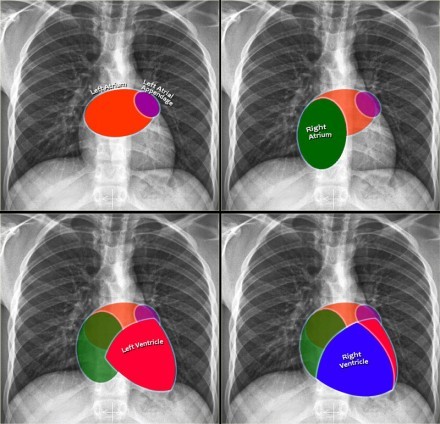

Seen as a small soft-tissue density adjacent to the lateral border of the aortic knob on a frontal radiograph in up to 10% of normal patients

Normally the left superior intercostal vein drains the left 2nd, 3rd, and 4th posterior intercostal veins and connects the left brachiocephalic vein and the accessory hemiazygous vein

As such, the left superior intercostal vein provides a collateral path of blood back to the heart

The size of the left superior intercostal vein is inversely related to the size of the accessory hemiazygous vein: the smaller (or absent) the accessory hemiazygous, the larger will be the left superior intercostal vein

The accessory hemiazygous vein (orange arrow below) drains the posterior intercostal veins from 3-4 intercostal spaces between the left superior intercostal vein (green arrow below) and the uppermost branch of the hemiazygous vein (blue arrow below)